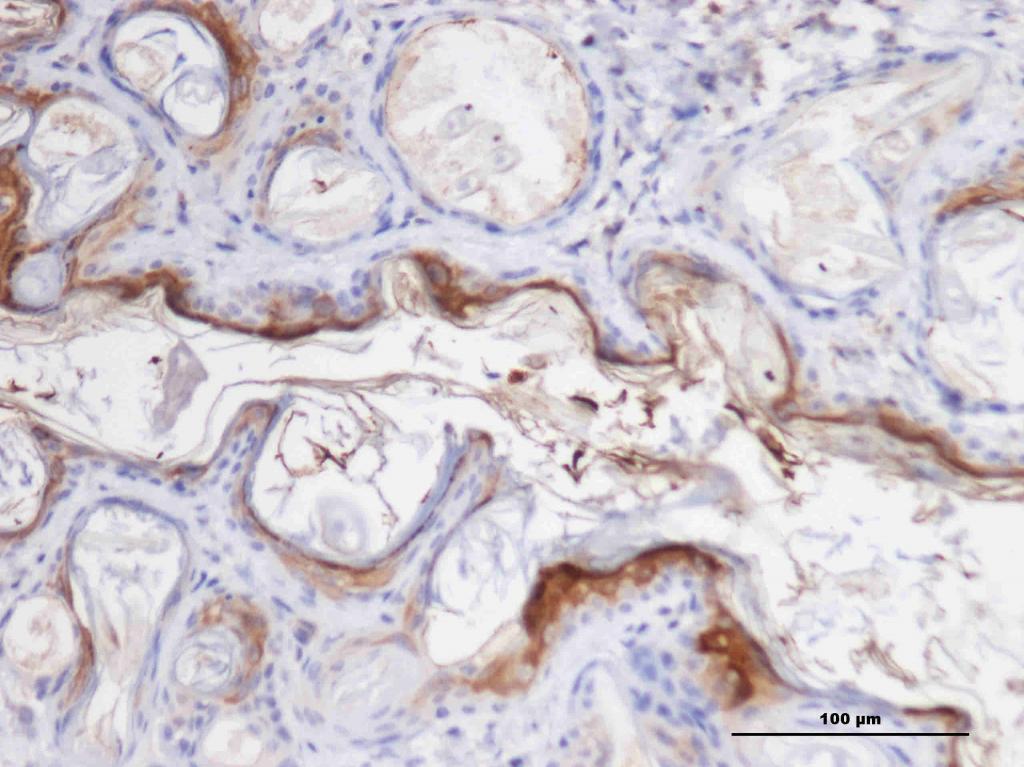

这两张图片是胰腺癌组织的VEGF抗体免疫结果,想问一下这两张的结果说明了哪些方面的区别?

本人是个菜鸟,不会看这结果,实验是外包给公司做的,所以请教各位大侠正解,或是有什么文献资料推荐就更好了,谢谢!

颜色深的(棕色)代表你要的抗体,越深,越多,说明抗体表达量高

不太像VEGF的着色

建议发一些低倍镜下的图看看

第一张是对照组吗?怎么也会有这么大范围的着色

第二张的着色不太像是免疫组化的正常着色

而且这几张图不太像是胰腺癌啊,所以最好要来低倍镜的图看整个的形态。

第一组是对照组的,那这是不是可以算是免疫组化实验失败了呀?

由于是外包给公司的,现在还没有拿到低倍镜的图。谢谢!

第二张挺像那么一回事 另外两张感觉像是非特异性染色